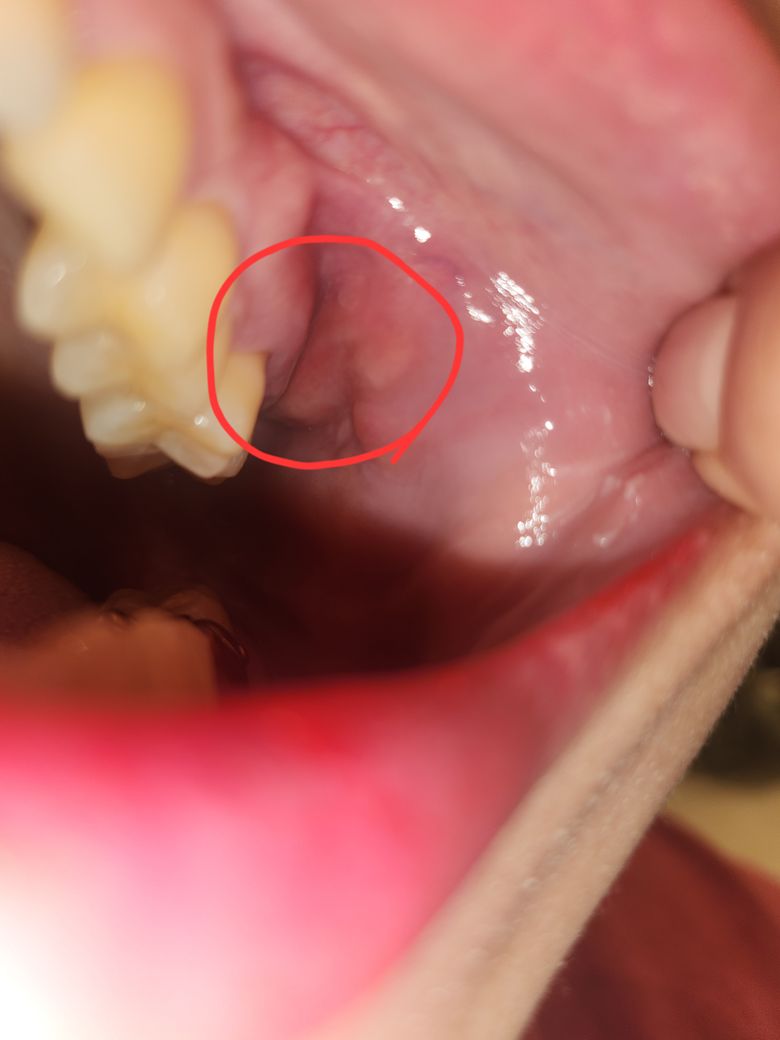

사랑니 발치 2주 지났는데 부었어요?

윗쪽 사랑니 발치 2주 됬습니다

누워있는거 아니고 똑바로요

잇몸이 갑자기 미친듯이 붓더니

진통제도 안들을만큼 미쳐버리게 아프더라고요

염증도 아니라고 하고

병원을 계속 방문해서 원인을 찾다가

사랑니 발치하면서

턱뼈? 잇몸뼈? 가 돌출되면서 계속 찔러서 그런거 같으시다면서 자리를 잡아가는 과정에 그럴수 있는데 보이지도 않게 안쪽에 있고 (실제로 손으로 만져서 찾으심)

빼기가 어려우시다면서 진통제로 몇일 참아보셔야 할꺼 같다고 하시더라구요 ㅠ

오늘 아침부턴 통증이 좀 가라앉긴 했는데

엄청 부은게 눈으로도 보이네요

잇몸쪽이랑 볼쪽이 부어서

앙을 하면 부은게 서로 밀어내는 느낌이 나면서 좀 아파용 ㅠ

약먹으면서 기다리는 방법밖에 없을까요....?

• 1번 째 사진